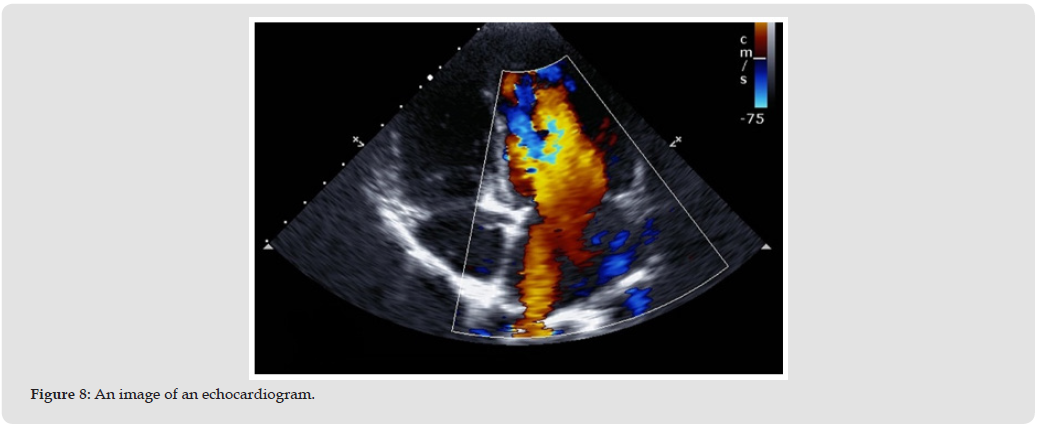

AI is already playing a vital role in diagnostic imaging in cardiology. It helps in patient selection for the right treatments and helps in diagnosis. DL has assisted in analysis of echocardiograms, cardiac